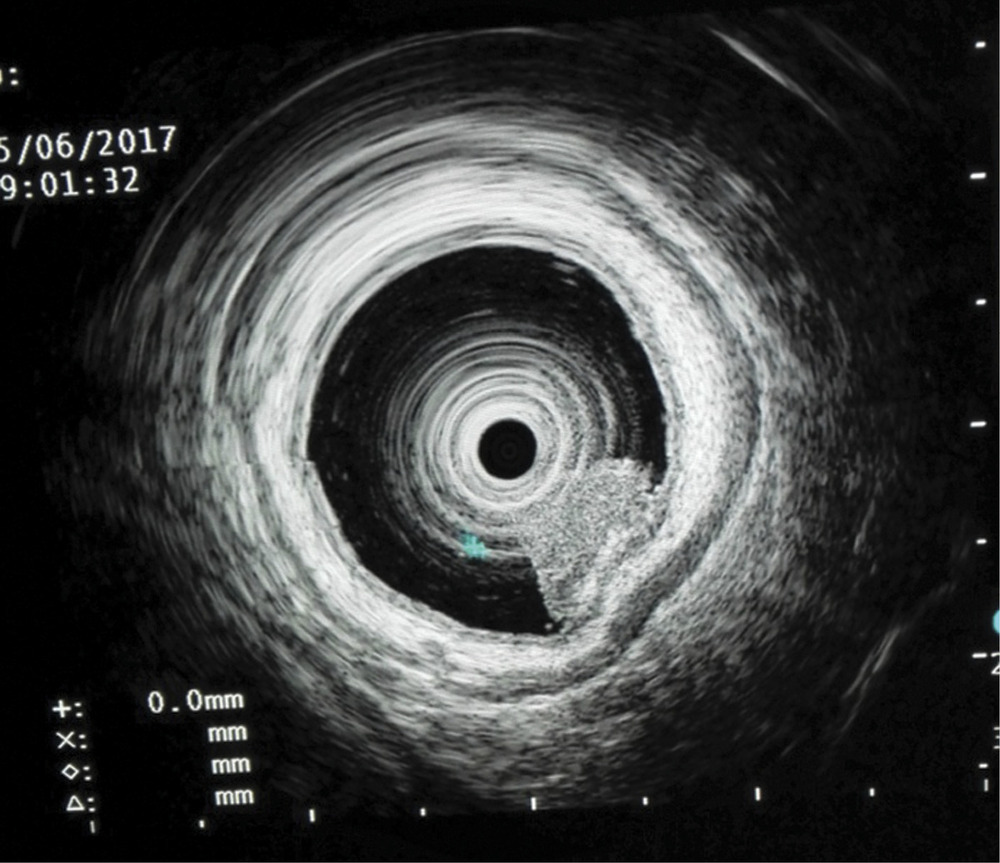

Исследование выполнялось при помощи видеоколоноскопа CF-HQ190L производства «Olympus» (Токио, Япония) и процессора серии EVIS Exera III. Эта система последнего поколения оснащена узкоспектральным режимом (NBI) и функцией увеличения изображения Near focus, которая позволяет выбрать нужную глубину резкости и получить более детализированное изображение слизистой оболочки и капиллярных сетей (рис. 3).